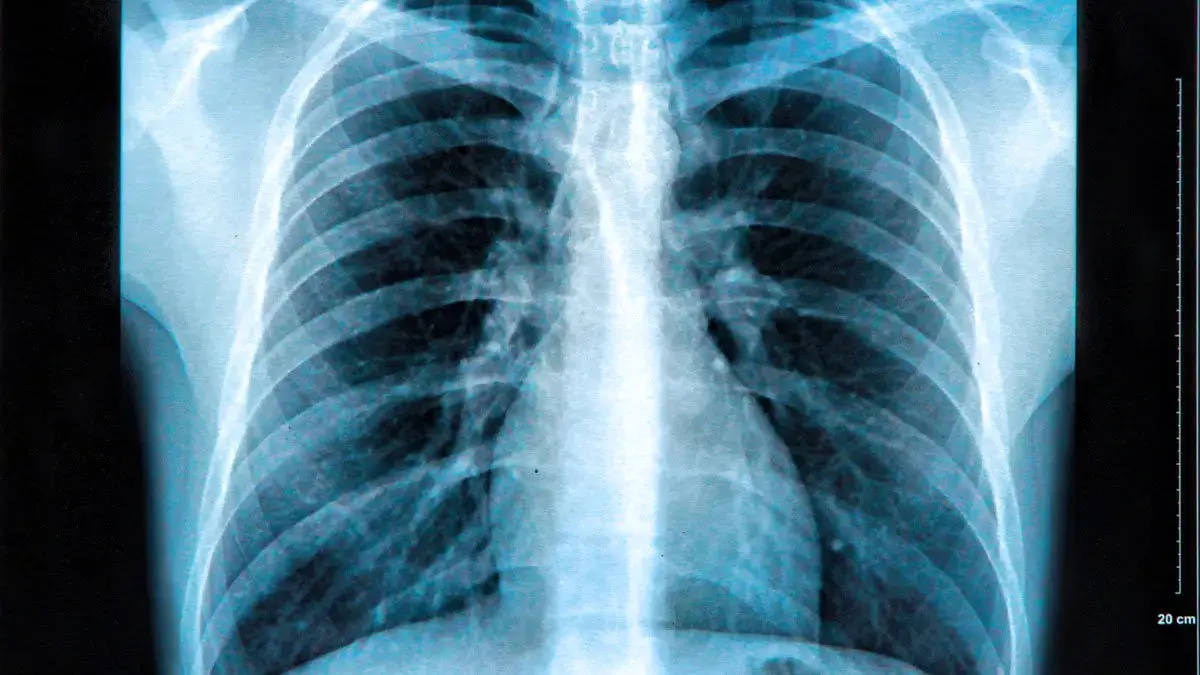

محققان سیستمی ساختهاند که میتواند از روی یک اسکن پرتو ایکس خطر سکته یا حمله قلبی در ۱۰ سال آینده بیمار را تشخیص دهد.